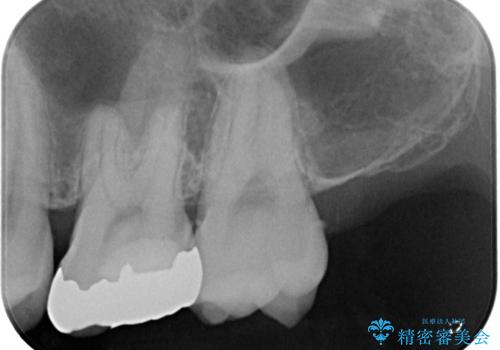

- 銀歯を外したいとのことで来院された患者様です。検査の結果、メタルインレーの範囲も大きいためオールセラミッククラウンにて補綴治療を行っていくことにしました。

拡大鏡視野下でメタルインレー、虫歯の除去を行いオールセラミッククラウンに適した形に整えました。